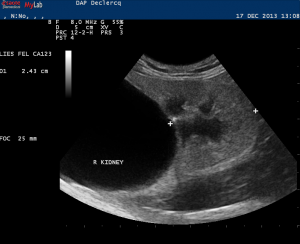

Que voit-on sur cette échographie?

kyste du rein= d’allure simple car lésion anéchogène avec renforcement postérieur non vasculaire sans végétations et à parois fines. (! Bosniak= définition scannographique!)